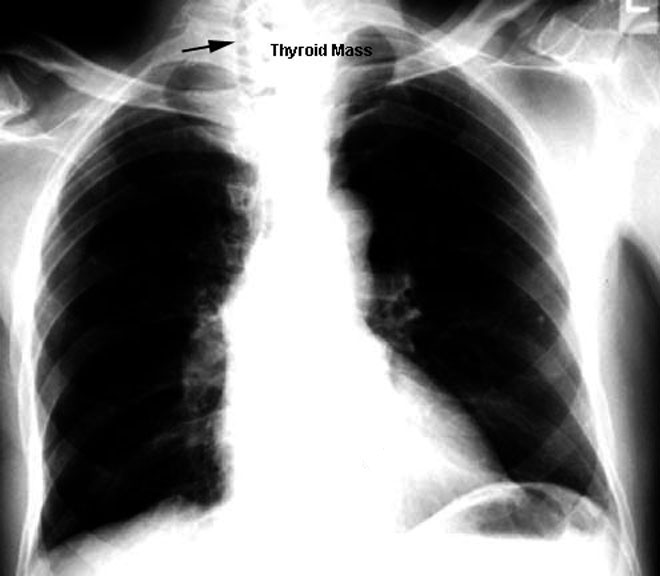

Tracheal Shift /

Thyroid Mass